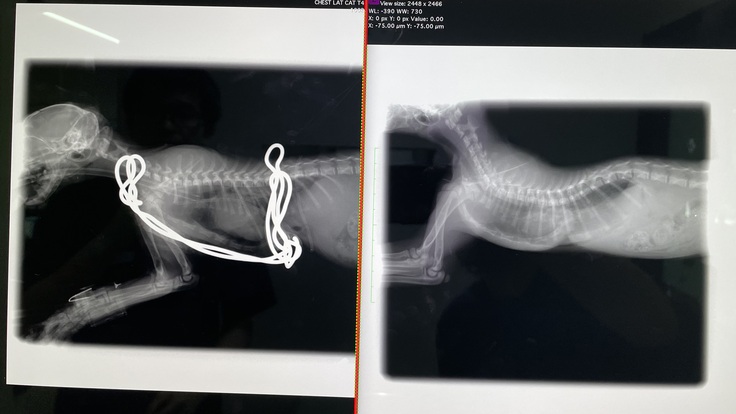

漏斗胸の胸骨矯正手術が無事に終わりました。

思ってたより骨が変形していたそうで、肋骨の軟骨もすごい形をしていたそうです。歪んでいた心臓も術後はほぼ正常な位置に戻りました。

すごく骨が変形していた為、完全には綺麗な形にはならなかったみたいです。成長していくにつれて、少しずつコルセット(ギプス)を調整していき、様子を見ていく、とのことでした。

※写真 (左)after (右)before